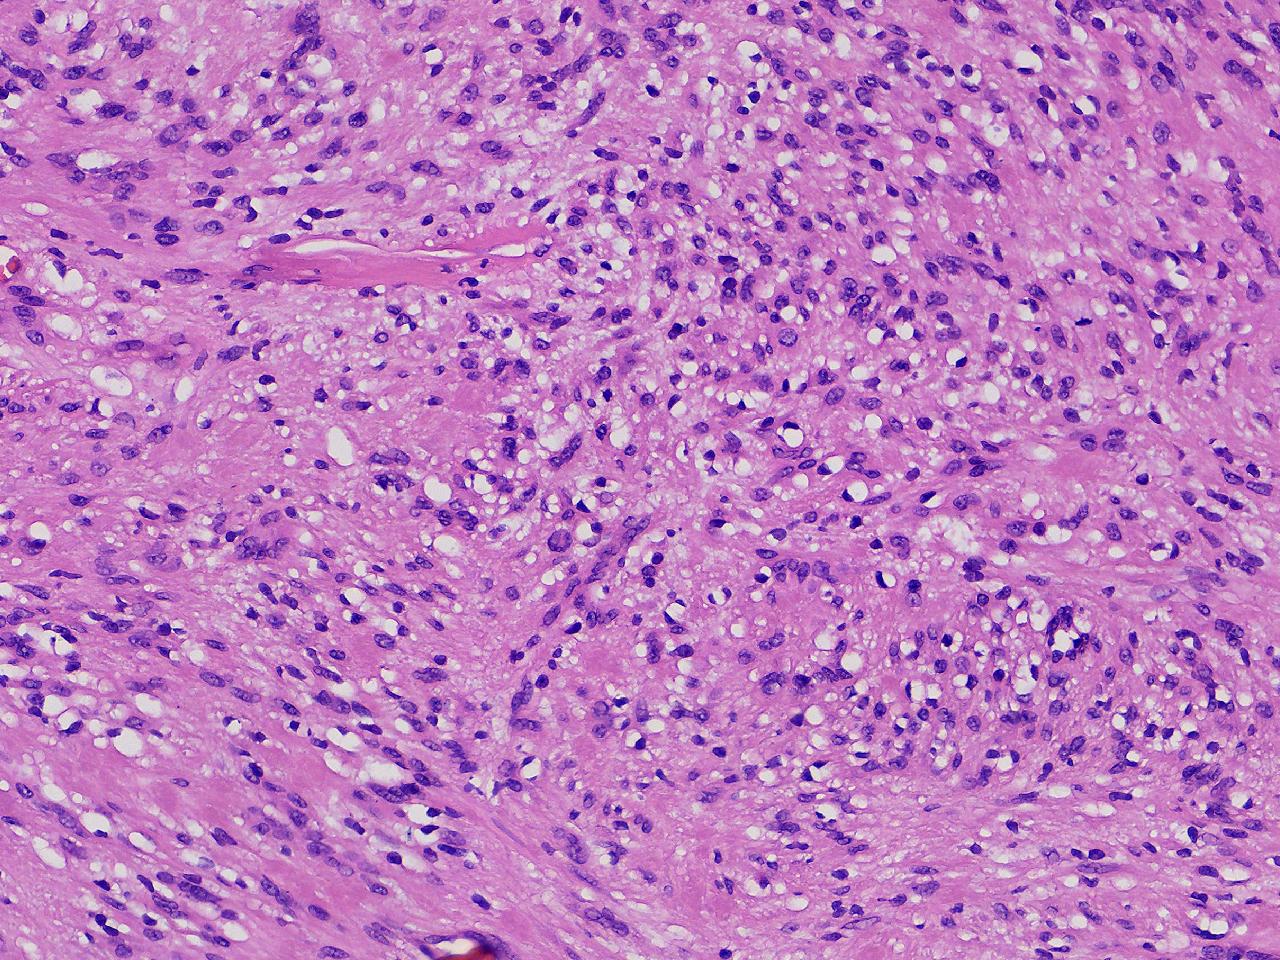

血管平滑肌瘤? 其他?

性别

女

年龄

76岁

临床诊断

右侧腰臀部皮下肿物

一般病史

右侧腰臀部皮下肿物1年余,无明显不适,逐渐增大。

标本名称

大体所见

卵圆形肿物一个,直径1.6厘米,上附皮肤。肿物切面灰黄实性,质中等。

考虑:结节性筋膜炎

神经鞘瘤。

建议除外平滑肌瘤,做IHC是更好的鉴别方式